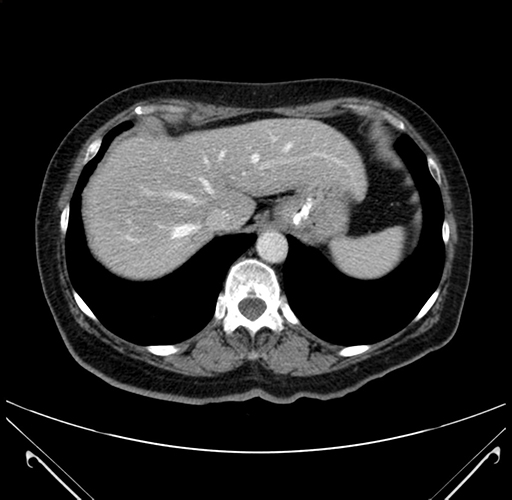

Axial Venous